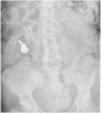

This report, details the case of a 61-year-old woman with a history of histrionic personality disorder and generalized anxiety disorder who developed severe pica, ingesting objects such as screws and jewelry. Initial psychiatric evaluations did not reveal a clear explanation for her behavior. However, further investigation identified significant cognitive decline, gait disturbances, and urinary incontinence—symptoms indicative of adult chronic hydrocephalus (ACH). A cranial CT scan confirmed ventricular dilation, leading to an ACH diagnosis. Pica disorder is often linked to frontal lobe dysfunction, common in ACH.

Este estudio describe el caso de una mujer de 61 años con antecedentes de trastorno de personalidad histriónica y trastorno de ansiedad generalizada, que desarrolló conductas severas de pica, mediante la ingesta de objetos como tornillos y joyas. Las evaluaciones psiquiátricas iniciales no revelaron una explicación coherente para su comportamiento. Sin embargo, una investigación más profunda, identificó la presencia de: deterioro cognitivo significativo, trastorno de la marcha e incontinencia urinaria, síntomas clásicos de hidrocefalia crónica del adulto (HCA). Una tomografía axial computarizada craneal confirmó la dilatación ventricular, lo que llevó al diagnóstico de HCA. El trastorno de pica a menudo se vincula con disfunción del lóbulo frontal, común en la HCA.